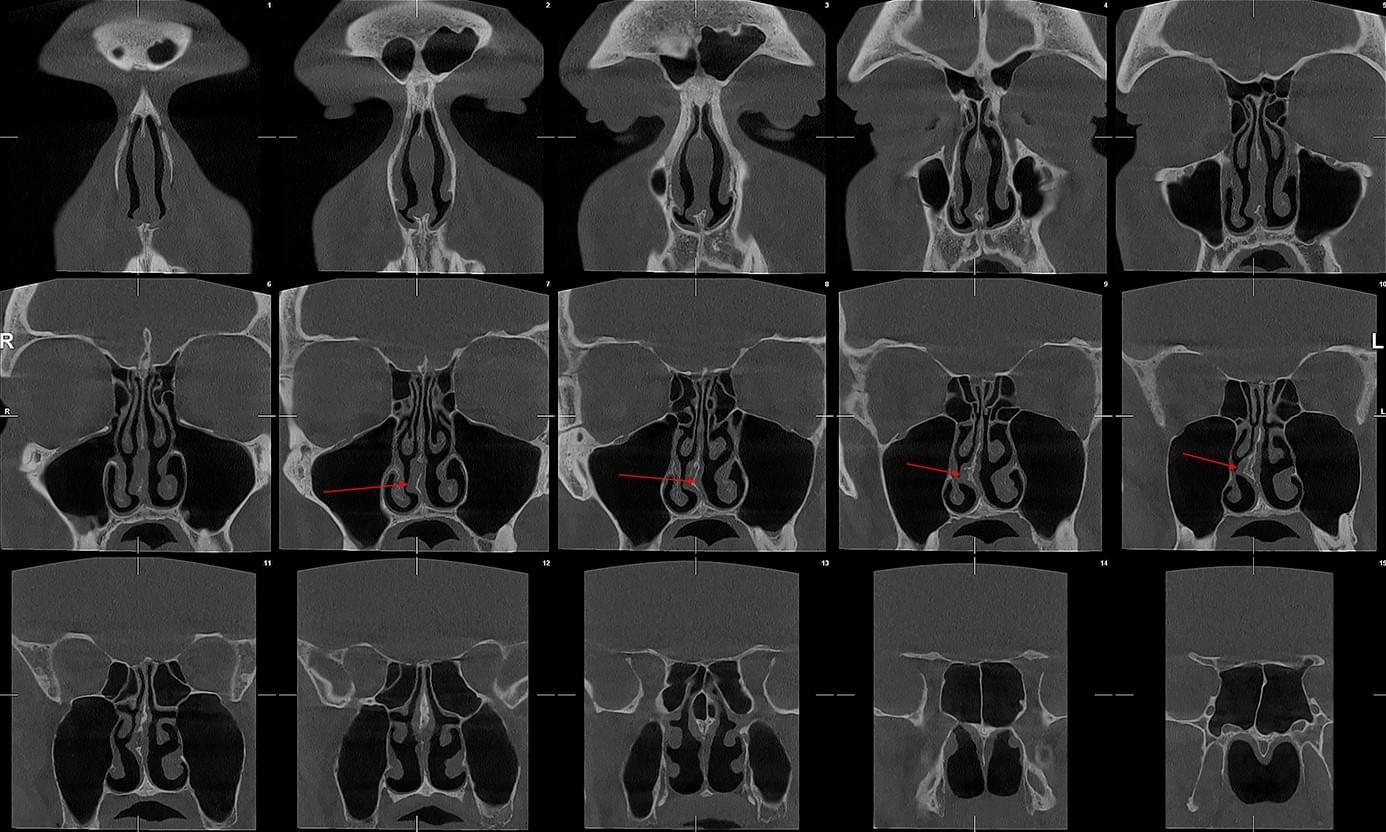

КПКТ (конусно-променева комп’ютерна томографія) — це 3D-знімок високої роздільної здатності. На відміну від звичайного рентгену, КТ показує: